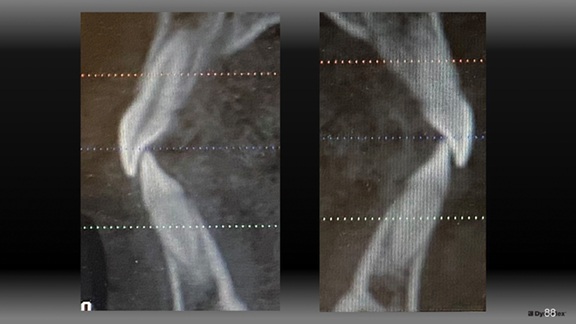

Figure 7 shows final records as treatment finished in 24 months. Notice in Figures 8 and 9 that the upper incisors rolled forward to a more ideal labiolingual inclination during this treatment.

Fig. 8

The Architects of the Lips: Part 4

Figure 12 shows that the lower incisors also rolled forward within her thick alveolar housing to couple with this more forward position of her maxillary incisors (pre-tx on the inside, post-tx on the outside). If she had a thinner type of housing, it might have impacted my tolerance for this movement.

Fig. 12